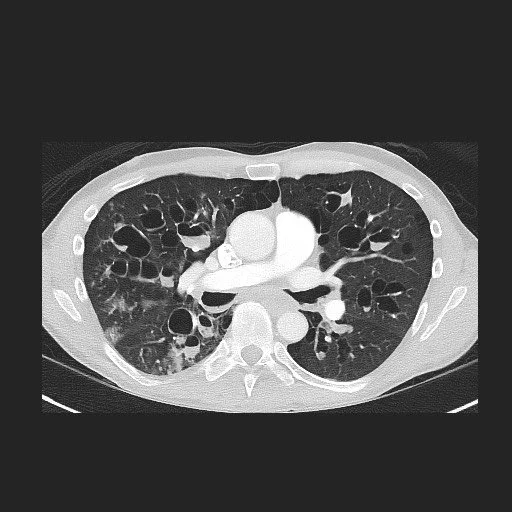

• Congenital cystic bronchiectasis due to failure of cartilage formation

• Diffuse bilateral bronchiectasis

• Affects mid and distal bronchi, trachea and proximal branches are normal

• Case courtesy of Michael P. Hartung, Radiopaedia.org, rID: 57467